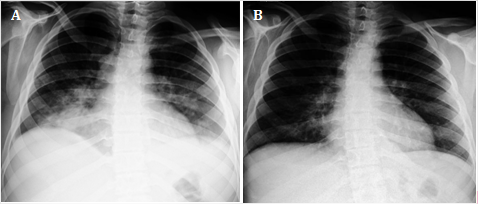

Sobre la base de lo planteado previamente, y gracias a la posibilidad de que la autora principal de esta epístola labora como especialista de imagenología en el mismo Hospital que los médicos investigadores del artículo en cuestión,1 se propone enriquecerlo con las radiografías realizadas a ese adolescente (fig.).

Desde el punto de vista radiológico, el paciente presentó características como las descritas en un estudio sobre niños afectados por la COVID-19, en quienes la consolidación pulmonar fue el signo más frecuente.5 Sin embargo, cabe destacar que este presentaba efusión pleural y distorsión del contorno cardiomediastinal, lo que sugiere la posible concomitancia de una infección bacteriana; si se clasificara según la BSTI, los hallazgos no estarían asociados a la COVID-19.

De ello se desprende la importancia de evaluar a cada paciente individualmente -su cuadro epidemiológico, los síntomas y comorbilidades- y de cumplir estrictamente el protocolo sanitario establecido en Cuba para la realización de la prueba de reacción en cadena de la polimerasa en tiempo real ante la existencia de infecciones respiratorias agudas graves.